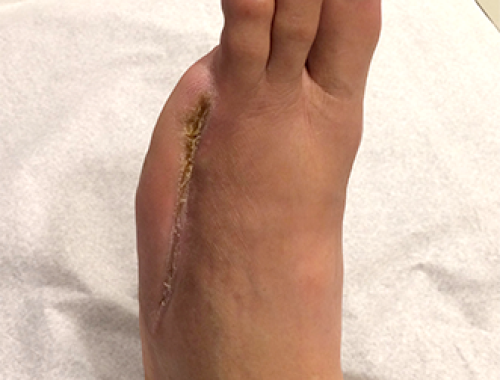

Revascularizações Periféricas

A falta de circulação para os diversos órgãos e membros pode ocorrer de maneira súbita ou gradual. As causas são as mais diversas, entre elas, trombose, aterosclerose, traumatismos, aneurismas, doenças inflamatórias, etc. Em alguns destes casos, a diminuição do fluxo sanguíneo determina um grave comprometimento à vitalidade do membro ou mesmo do órgão. Após detalhada avaliação do caso pelo cirurgião vascular, este pode indicar um procedimento de revascularização.

Através de pontes com material sintético ou biológico (safenas) é possível reestabelecer a circulação aos segmentos mais comprometidos, impedindo a perda do membro ou do órgão. Atualmente também é possível realizar estes procedimentos de forma minimamente invasiva através da cirurgia endovascular.